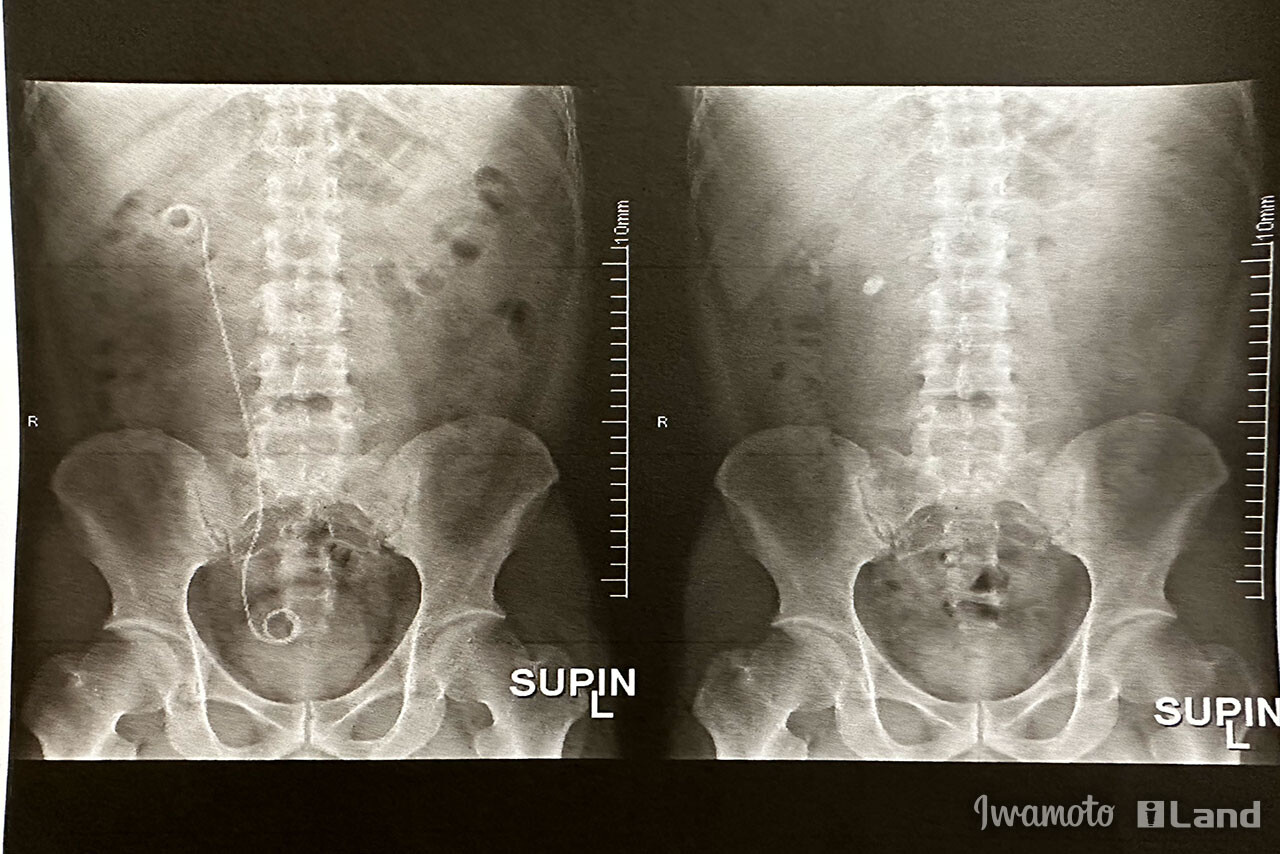

術前術後のレントゲン比較。

【左】術後。石の影がなくなり、尿路形成確保のステントが入っているのが判る。

【右】術前。腎臓の所に石があるのが判る